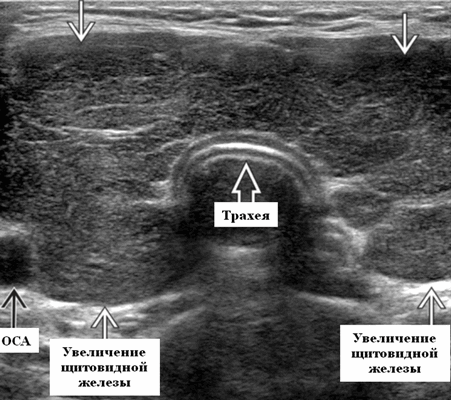

Диффузный нетоксический зоб. Болезнь характеризует увеличение железы из-за нехватки поступления йода с пищей при повышенном расходе элемента в подростковом возрасте, в период гестации или при врожденном изменении клеток-тиреоцитов, которые утрачивают способность забирать йод из крови. На сонограммах видны множественные мелкие фолликулы-пузырьки с анэхогенным сигналом.

Диффузный токсический зоб. Патология развивается на фоне аутоиммунных нарушений или опухолей гипофиза, что приводит избыточному производству тиреотропного гормона. На УЗИ щитовидная железа увеличена в 2-3 раза, видны участки пониженной эхогенности. В режиме допплерографии обнаруживаются цветные прилегающие друг к другу точки. Типичные признаки:

- волнистый контур;

- умеренная гипоэхогенность паренхимы;

- усиление кровотока;

- неоднородность эхоструктуры.

- Легкое / умеренное диффузное, симметричное увеличение щитовидной железы, включая перешеек на УЗИ

- Увеличение в объеме щитовидной железы ≤ 90 мл

- Картина эхоструктуры паренхимы: гипоэхогенная, гетерогенная, «пятнистая»

- Гипоэхогенность паренхимы обусловлена уменьшением коллоидного содержимого и увеличение клеточного состава с уменьшением коллоидно-клеточного соотношения ± гиперваскулярность

Лучший диагностический метод при данной патологии - УЗИ. На нем регистрируется увеличенная железа, гипоэхогенная, гетерогенная картина ее внутренней эхоструктуры и увеличение паренхиматозной васкуляризации. Размер щитовидной железы имеет легкое или умеренное увеличение в размере. Как проводят ультразвуковую диагностику при болезни Грейвса? Необходимо использовать преобразователь с высоким разрешением, частота сканирования ≥ 7,5 МГц. Сканирование в продольной и поперечной плоскостях, включая доплеровское исследование.

Серошкальное УЗИ при болезни Грейвса. Легкое или умеренное диффузное, симметричное увеличение щитовидной железы, включая перешеек. Увеличение в объеме щитовидной железы ≤ 90 мл. Нормальный объем: новорожденный 0,4-1,4 мл, увеличение на 1,0-1,3 мл на каждые 10 кг веса, до нормального объема 10-11 (± 3-4) мл у взрослых. Гипоэхогенный, гетерогенный, «пятнистый» паттерн паренхиматозной эхоструктуры. Гипоэхогенность паренхимы обусловлена снижением коллоидного содержимого и увеличением клеточного состава с уменьшением коллоидно-клеточной границы ± гиперваскулярность. Гипоэхогенность паренхимы связана с частотой позитивности антител к рецептору ТТГ (TRAb). Сохранение гипоэхогенности паренхимы при прекращении лечения, связанного с рецидивом гипертиреоза